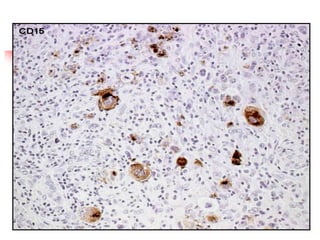

Mixed cellularity, CD15+ RS cells

IMMUNOPHENOTYPE OF

RS CELL in Classical HL

 CD 15 +

 CD 30 +

 CD 20 -

 CD 45 -